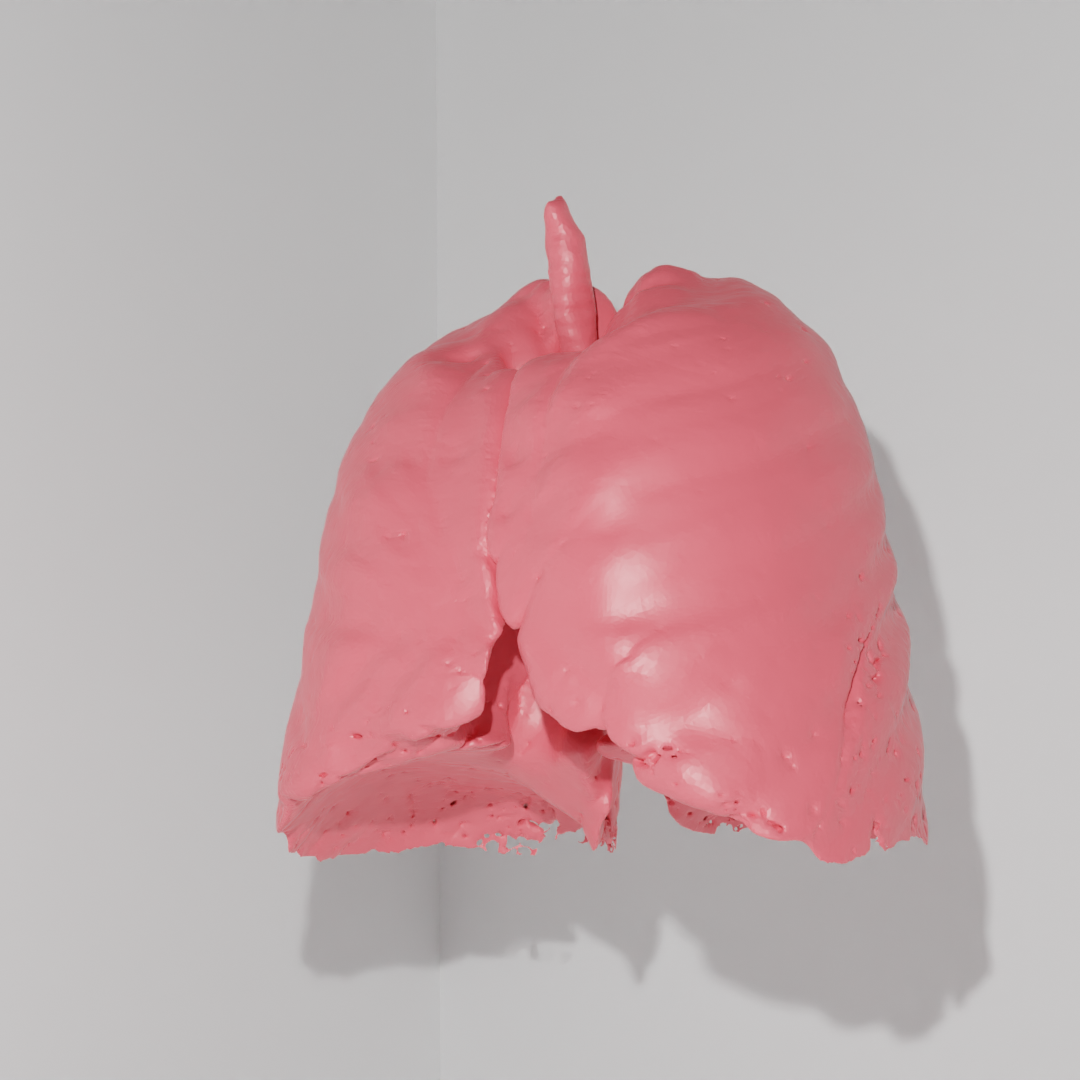

modele dróg oddechowych – projekt i wydruk 3D z żywicy epoksydowej i innych

więcej na temat projektu: UWM